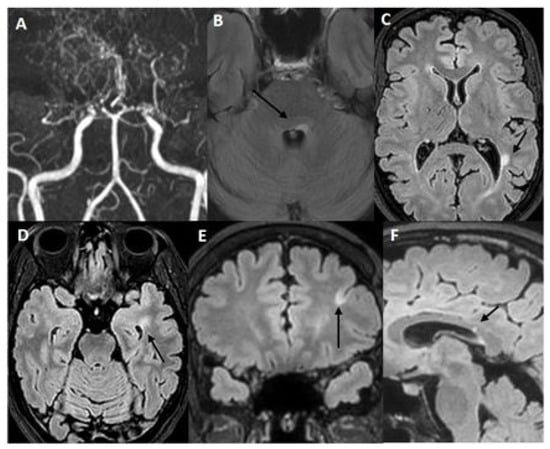

2.2. Case 2: A 43 Years-Old Woman Was Evaluated in Our Institute Because of the Neuroradiological Finding of Unilateral MMA

| Our Case 2 | Italy/ Caucasian | 43/F | Left hemi-anesthesia (transient, recurring) | Bilateral supratentorial periventricular with corpus callosum involvement, left cerebellar hemisphere; bulbospinal tract; cervical spine | Brain: − Spine: − | + | + | − | AntiAQP4 (−) Anti-ds DNA-ANA-ENA-ANCA-Anti cardiolipin and beta2GP(−) G20210A Factor II and MTHFRC1677T (heterozigosis) Total body PET (−) | Left MCA and distal ICA steno-occlusion, MM network | MMA + MS | no | Aspirin | Dimethylfumarate Glatiramer acetate Teriflunomide | 8 years |